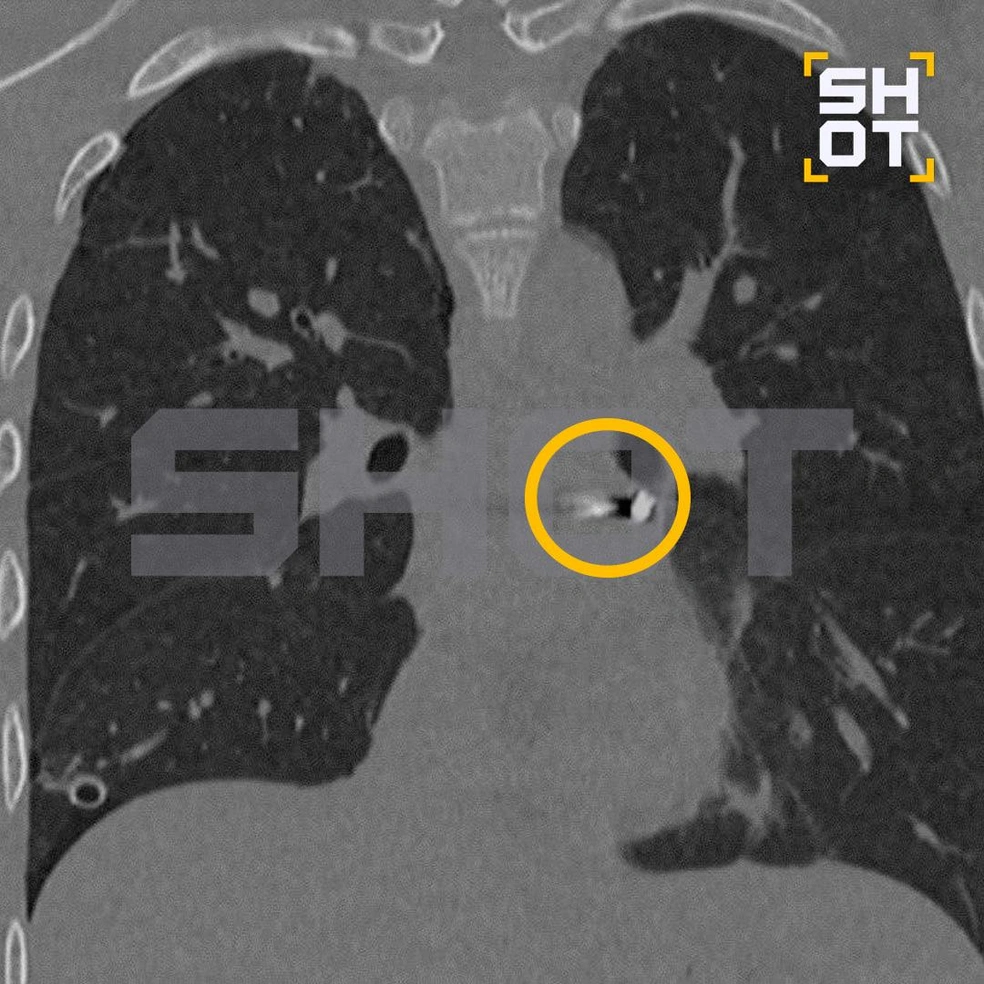

В Подмосковье спасли подростка с пулей в сердце

В Подмосковье 16-летний подросток получил проникающее ранение груди от пневматического ружья. Несчастный случай произошел, когда молодой человек решил пострелять с друзьями, пуля случайно попала ему в сердце.

Подростка срочно доставили в Детский центр им. Рошаля, где медики обнаружили пулю в полости перикарда, наружной оболочки сердца. Состояние было критическим, и пациента направили на экстренную операцию.

Пуля находилась рядом с сердцем

Хирургам пришлось работать в крайне сложных условиях, манипулируя инструментами в миллиметрах от жизненно важных структур сердца, которое постоянно двигалось. Несмотря на сложности, врачам удалось удалить пулю без единого разреза, проведя малоинвазивное вмешательство.

Подросток находится в стабильном состоянии, что считается настоящим чудом после такого серьезного ранения.